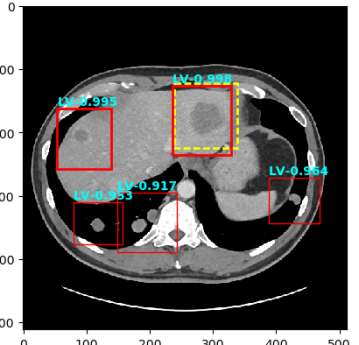

Figure 4: Six sample detection results are illustrated with the annotation lesion patches as yellow dashed boxes. The outputs from our proposed detection framework are shown in colored boxes with LiVer lesion (LV) in Red, Lung Nodule (LN) in Orange, ABdomen lesion (AB) in Green, Chest Lymph node (CL) in magenta and other MiXed lesions (MX) in blue. (a) Four lung lesions are all correctly detected; (b) Two lymph nodes in mediastinum is presented; (c) A Ground Glass Opacity (GGO) and a mass are detected in the lung; (d) An adrenal nodule; (e) Correct detections on both the small abdomen lymph node nearly aorta but also other metastases in liver and spleen; (f) Two liver metastasis are correctly detected. Three lung metastases are detected but erroneously classified as liver lesions .